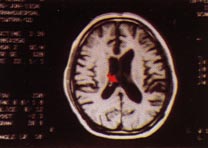

3.CT掃描:不但可定位,並可顯示腫瘤的大小、形狀及腦組織、腦室的改變、特別易於發現多發性腫瘤、腫瘤類圓形或形狀不規則,呈高密度或混雜密度影像,混雜密度者常為腫瘤內有壞死囊變,則顯示有低密區。強化後大多有明顯的塊狀或環狀影像增強、腫瘤周圍常有低密度腦水腫帶。可見腦室受壓變形,小腦腫瘤可見第三腦室以上對稱擴大。